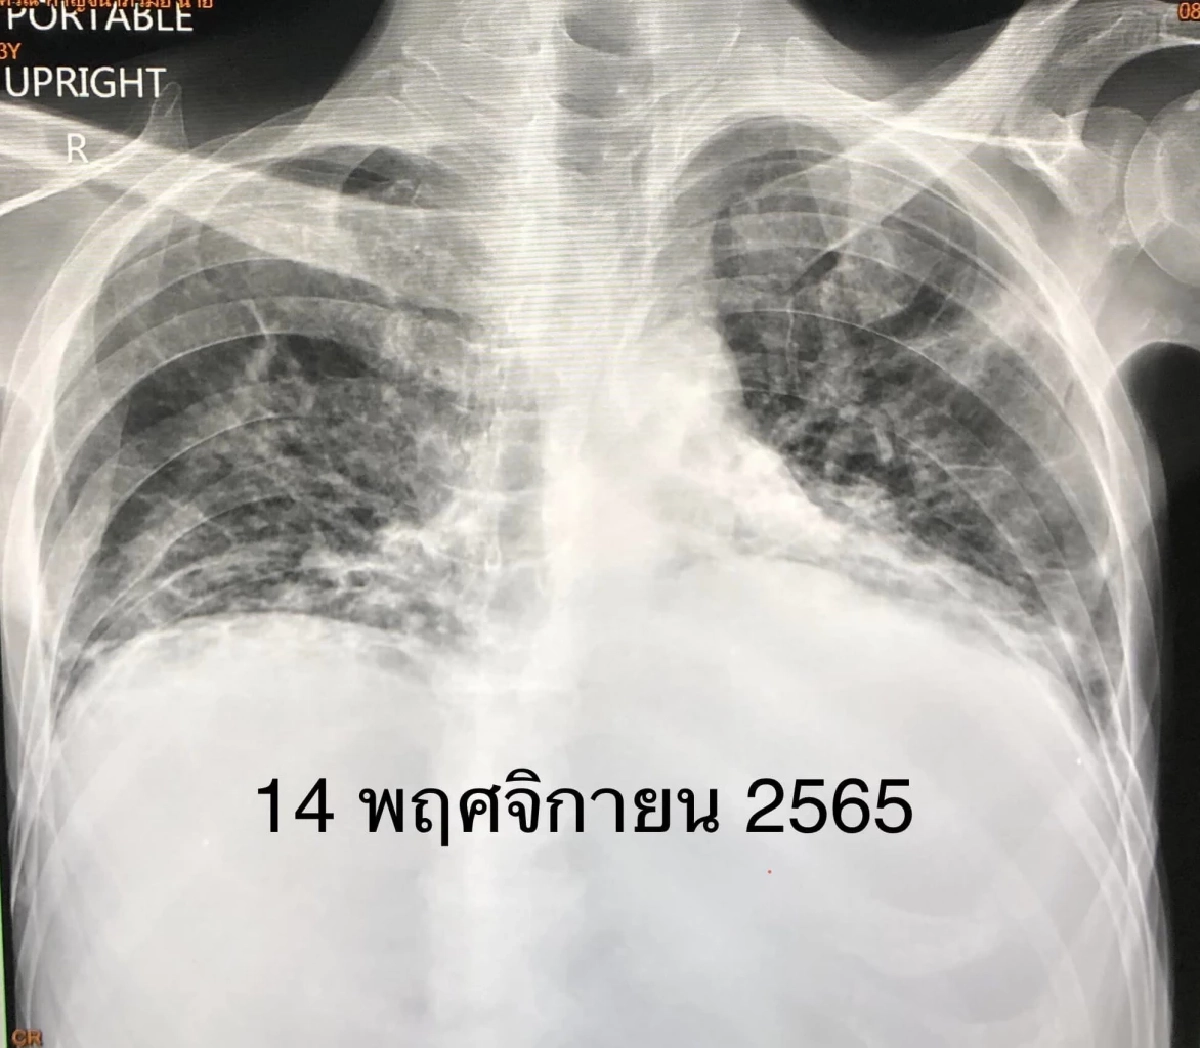

ผู้ป่วยชายอายุ 53 ปี เป็น มะเร็งเม็ดเลือดขาว 3 ปี ฉีดวัคซีนป้องกัน โรคโควิด แอสตราเซเนกา 2 เข็ม และไฟเซอร์ 1 เข็ม เริ่มมีไข้สูง ไอ เจ็บคอ 3 วัน ตรวจ ATK ให้ผลบวก เหนื่อยมาก เข้าโรงพยาบาลวันที่ 28 ตุลาคม 2565 ระดับออกซิเจนที่ปลายนิ้วต่ำมาก 80% เอกซเรย์ปอดมีฝ้าขาวทั้ง 2 ข้าง ตรวจรหัสพันธุกรรม 22 สายพันธุ์ พบ ไวรัสโควิด RT-PCR SARS-CoV-2 CT value 17.1 ไม่พบไวรัสตัวอื่น เข้าห้องไอซียู ให้ออกซิเจนชนิด high-flow nasal cannula (HFNC) ให้ ยาเรมเดซิเวียร์ และยาสเตียรอยด์ชนิดฉีดเข้าเส้นเลือดดำ

คนไข้ไม่ดีขึ้น เหนื่อยมากขึ้น เอกซเรย์ปอดแย่ลง ต้องใส่ท่อหายใจ และเครื่องช่วยหายใจ ความดันตำ่จนช็อกในวันที่ 30 ต.ค. 2565 ต้องให้ยาเพิ่มความดัน แต่หลังจากการรักษา คนไข้อาการดีขึ้นช้าๆ ความดันดีขึ้น ไข้ลง เหนื่อยลดลง ในที่สุดถอดเครื่องหายใจได้วันที่ 4 พ.ย. 2565 แต่ยังต้องใช้ออกซิเจนเสียบจมูก ได้ยาฉีด เรมเดซิเวียร์ และสเตียรอยด์ครบ 10 วัน

วันที่ 9 พฤศจิกายน ตรวจ ATK ซ้ำให้ผลลบ ระดับออกซิเจนปลายนิ้วขึ้นมา 96% เอกซเรย์ปอดดีขึ้นช้าๆ